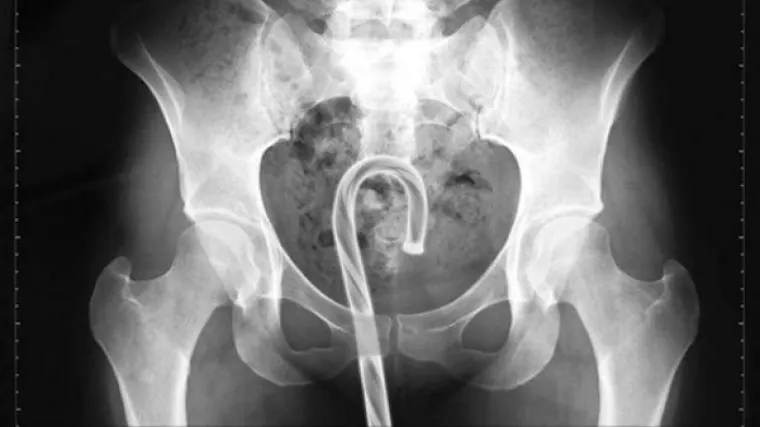

LJUDI SU ČAROBNO SPREMIŠTE, U NJIH STANE BAŠ SVE: Nevjerojatne snimke pokazuju što su sve uspjeli ugurati u sebe